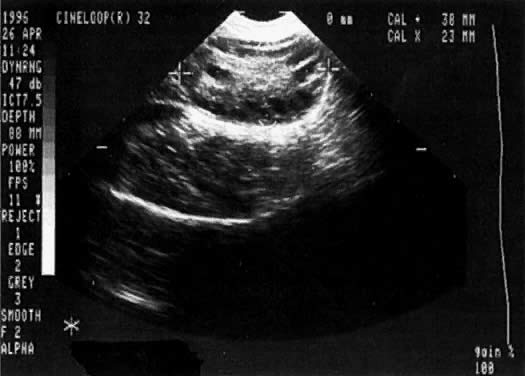

Polycystic ovaries are characterized by multiple subcapsular follicular cysts (2 to 10 mm) and a thickened capsule, and are enlarged both due to the preceding factors and to increased central stroma. They have a characteristic appearance on transvaginal ultrasound according to the frequently cited criteria of Adams and co-workers,44 which includes the presence of eight or more peripheral follicular cysts (less than or equal to 2 to 10 mm) with increased central ovarian stroma (Fig. 2). Polycystic ovaries represent a final common phenotype of a wide variety of etiologies or, as Givens45 stated so succinctly, they are “a sign, not a diagnosis.” Although polycystic ovaries have been associated with a wide variety of apparently unrelated conditions (Table 3), many practitioners use the presence of polycystic ovaries as a screening test for PCOS. However, their presence also can be found in normoinsulinemic, normoandrogenic, cycling women. Hyperandrogenism has frequently been associated with polycystic ovaries, although there are many other pathologic entities without overt hyperandrogenism that may also be associated with polycystic ovaries. Recently, women with glycogen storage disease (types IA and III), a syndrome of insulin resistance without hyperandrogenism, were noted to have polycystic ovaries.46 All females, including children, were noted to have polycystic ovaries. Both prepubertal and postpubertal females were noted to have normal levels of circulating androgens. This association suggests that in certain instances insulin resistance alone can cause polycystic ovaries.

Fig. 2. Polycystic ovary morphology on transvaginal ultrasound. Note the multiple small 2- to 10-mm subcapsular follicles with increased, dense central stroma.

Insulin resistance is characteristic of PCOS, or otherwise stated, the syndrome of hyperandrogenism and menstrual irregularity; however, it is not found in endocrinologically normal women with polycystic ovary morphology, or in hyperandrogenic women with ovulatory cycles.47,48,49 Additionally, women who have all the endocrinologic manifestations of the syndrome, including insulin resistance, can have normal ovarian morphology on ultrasound.50 Polycystic ovaries are a puzzling phenomenon: their presence or absence may not be relied upon to make the diagnosis of hyperinsulinemic hyperandrogenism.